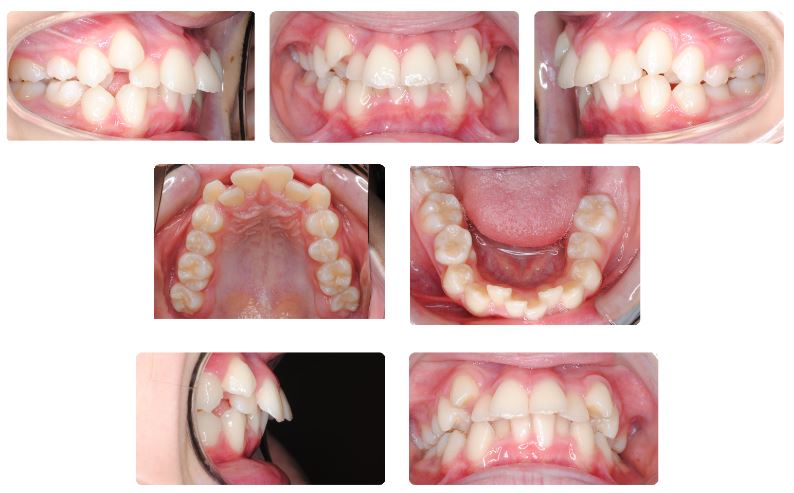

下顎後退を伴う八重歯で噛み合わせの深い症例  10代前半

主訴:八重歯の見た目が気になる

初診時年齢:12歳

性別:女性

診断名:下顎後退をともなう犬歯低位唇側転位

抜歯/非抜歯:抜歯

装置名:マルチブラケット装置

治療費用:約62万円(税抜)と来院時に調節料5,000円(税抜)

治療期間:2年1ヶ月

治療に関する副作用/リスク:歯の移動時の痛み  装置による口腔粘膜の口内炎

前歯の歯並び、特に八重歯が気になるとのことで来院されました。

乳歯が一部残存している時期でしたが、この症例では口元の突出を避けるため上下あごの小臼歯抜歯を選択してワイヤーによる固定式矯正装置で治療を進めました。

治療期間は2年1ヶ月でした。

萌出途中であった上下顎の最後臼歯(第二大臼歯)をしっかり咬ませるのに時間を要しました。